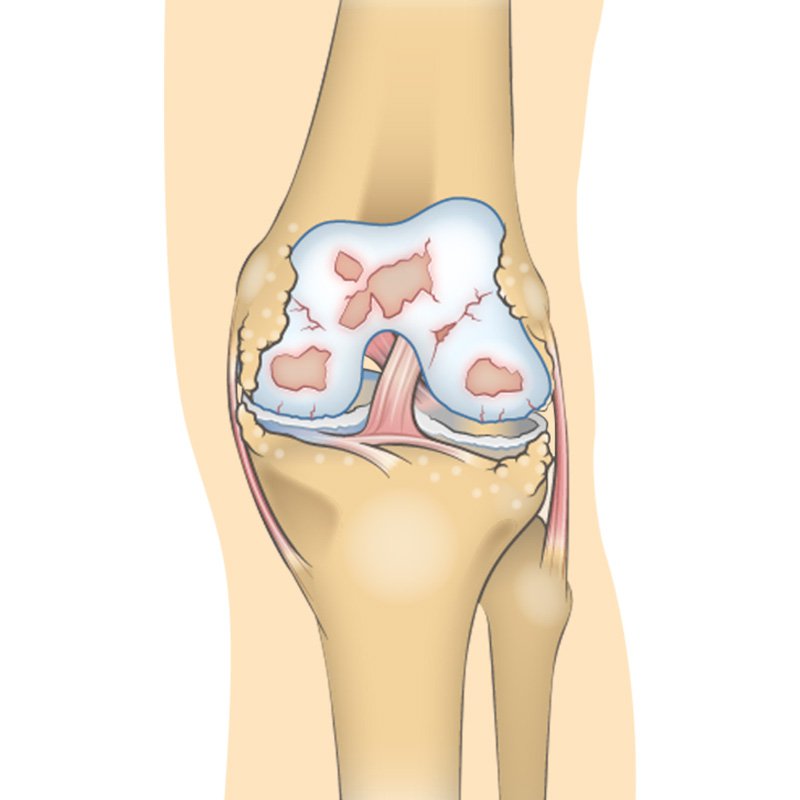

Over time osteoarthritis affects the bone cartilage and synovial fluid of the knee. With moderate knee OA, changes in the joint are much more evident the cartilage surface between the bones has begun to a road narrowing the gap between the femur and the tibia. hyaluronic acid which helps synovial fluid lubricate the joint is now becoming less viscous elastic and concentrated. Osteoarthritis often affects the sub-chondral bone Located just underneath the cartilage. Some contraband provides hydration and oxygen to the cartilage. Osteo fights may increase in number and size making the bone rougher. All these factors combined to make joint pain more severe and long-lasting both with movement and at rest. OA conditions worsened dramatically the joint spaces become far narrower causing more rapid and severe destruction of the cartilage in the knee becomes inflamed and sore. Synovial fluid is decreased increasing friction and pain during movement. Osteo fights continue to develop bone moves against bone not cartilage mobility activities of daily living and quality of life are severely impacted.”

The joint space between the bones will be dramatically reduced, the cartilage will almost be completely gone and the synovial fluid will be decreased. This stage is normally associated with high levels pain and discomfort during walking or moving the joint.